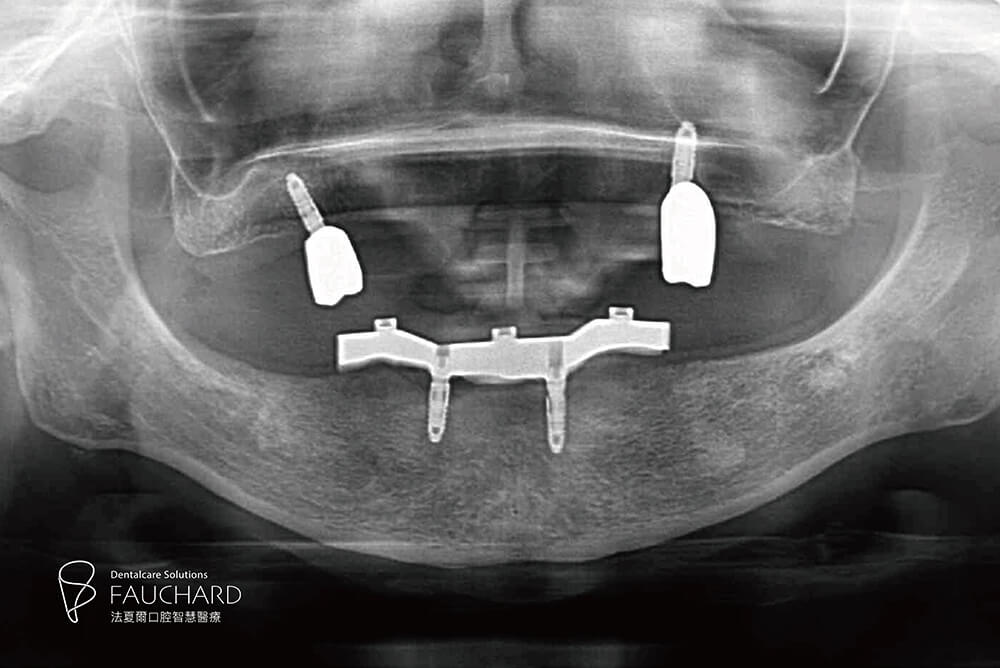

2. 全口重建》All-on-4 系列-當天有牙速效方案

手術當日有牙,咬合如真牙。適合經醫師評估可手術的全口無牙/大範圍缺牙患者。

「All-on-4 全口重建」是葡萄牙 Dr. Paulo Malo 教授與知名植體品牌諾保科 (NOBEL BIOCARE) 研發的植牙技術。「All-on-4 全口重建」利用建築中斜張橋設計原理,僅需在顎骨植入 4 根植體即可支撐單顎整排假牙。

| 植體數量 | 上下顎各 2 根植體 | 4 / 6 / X +顴骨植體 | 無 |

| 假牙類型 | 活動假牙或卡扣型假牙 | 上下顎整座固定假牙 | BPS 吸附式活動假牙 |